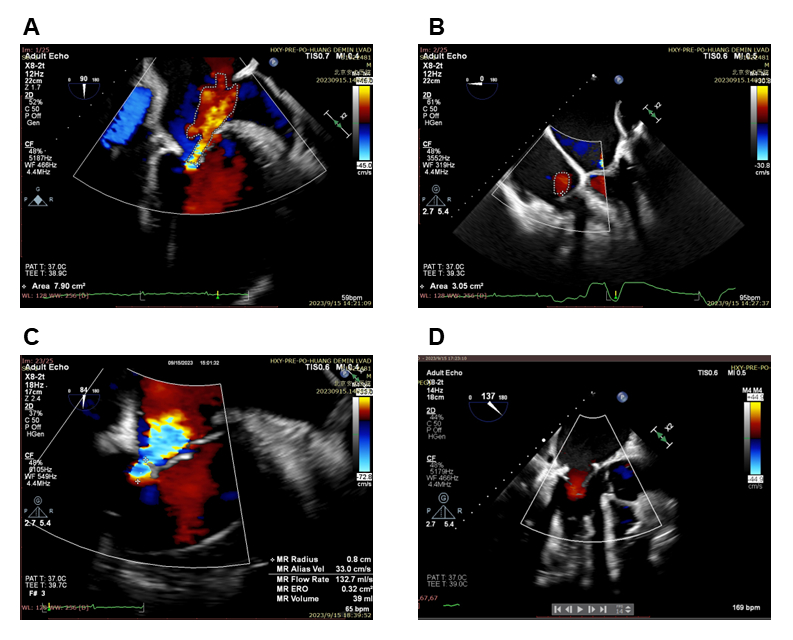

Corheart 6 Ultracompact Magnetically Levitated Left Ventricular Assist Device in a Patient with Obese Heart Failure

Abstract Body (Do not enter title and authors here): Due to the critical shortage of cardiac transplant donors, durable left ventricular assist device (LVAD) has become an effective alternative therapy for end-stage heart failure (ESHF). Miniaturization of LVAD holds significant clinical implications. This report describes the clinical application of the novel 90-gram Corheart 6 ultra-compact axial-flow magnetically levitated LVAD. A 55-year-old male patient with ESHF and high-body mass index (BMI) successfully underwent Corheart 6 implantation. During the 601-day follow-up period, no device-related adverse events were observed. The successful application in this high-BMI patient demonstrates the excellent stability of the Corheart 6 miniaturized magnetically levitated LVAD, highlighting its potential for future minimally invasive implantation techniques and pediatric applications